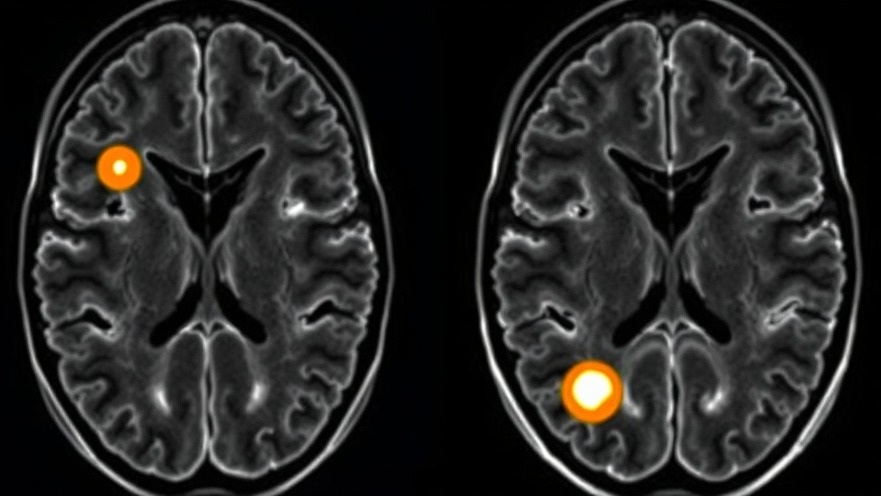

Recognize Pituitary Tumors Symptoms: A Guide for Wellness Practitioners

Understanding Pituitary Tumors: The Hidden Signs

The pituitary gland, often called the 'master gland' of the body, plays a pivotal role in regulating essential hormonal functions. However, when tumors develop in this small yet influential gland, the consequences can be multifaceted and often severe. For concierge medical practice owners focused on wellness, recognizing the signs and symptoms of pituitary tumors is crucial not only for patient care but also for enhancing overall health strategies.

Symptoms of pituitary tumors can be subtle and may develop over time, resulting in delays in diagnosis. Early detection is vital, as symptoms can be categorized based on whether the tumor is functioning (hormone-producing) or non-functioning. Non-functioning tumors might not show symptoms until they grow large enough to cause pressure on adjacent tissues.